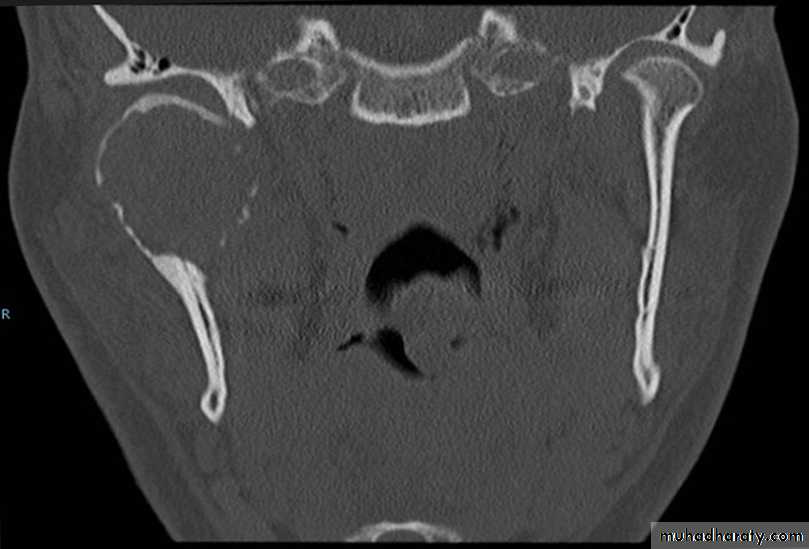

Bilateral Ankylosis

Dr. Mohammed Amjed Alsaegh, 2021

24

1. The mandible is symmetrical but micrognathic.2. The patient develops a typical bird face deformity with receded chin.

3. Inability to open the mouth.

4. The neck chin angle is greatly reduced. The defect can be so grievous that sometimes the neck chin angle is absent.

5. Antegonial notch is well defined bilaterally.

6. Upper incisors are often protrusive with anterior open bite. Maxilla may be narrow.

7. Multiple carious teeth with bad periodontal health can be seen.

8. Severe malocclusion.

9. Crowding with many impacted teeth is seen on a radiograph.